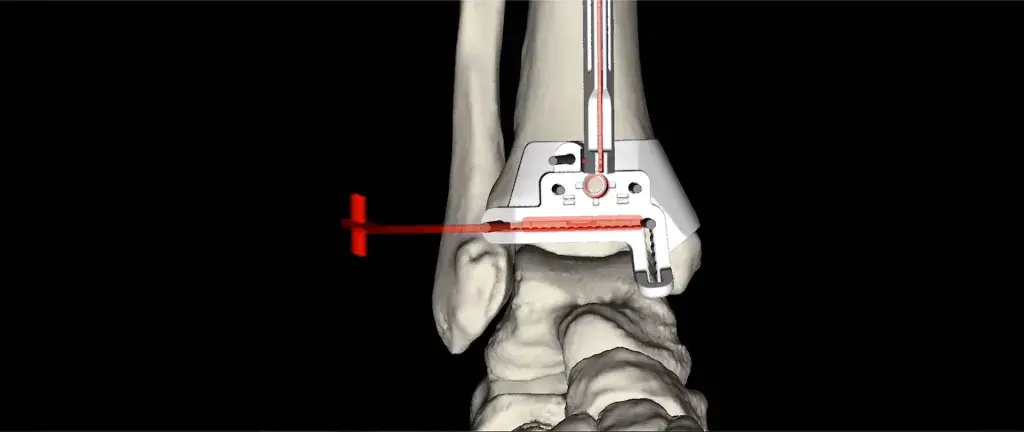

Patient-Specific Solutions

3D Systems partners with device manufacturers and healthcare providers to transform surgical outcomes for both patients and surgeons. We create custom solutions that help translate virtual surgery into the OR with the goal of improving outcomes and the overall patient experience. Our multifaceted offerings include advanced design and planning software, expert planning services and a full range of custom implants and instrumentation.